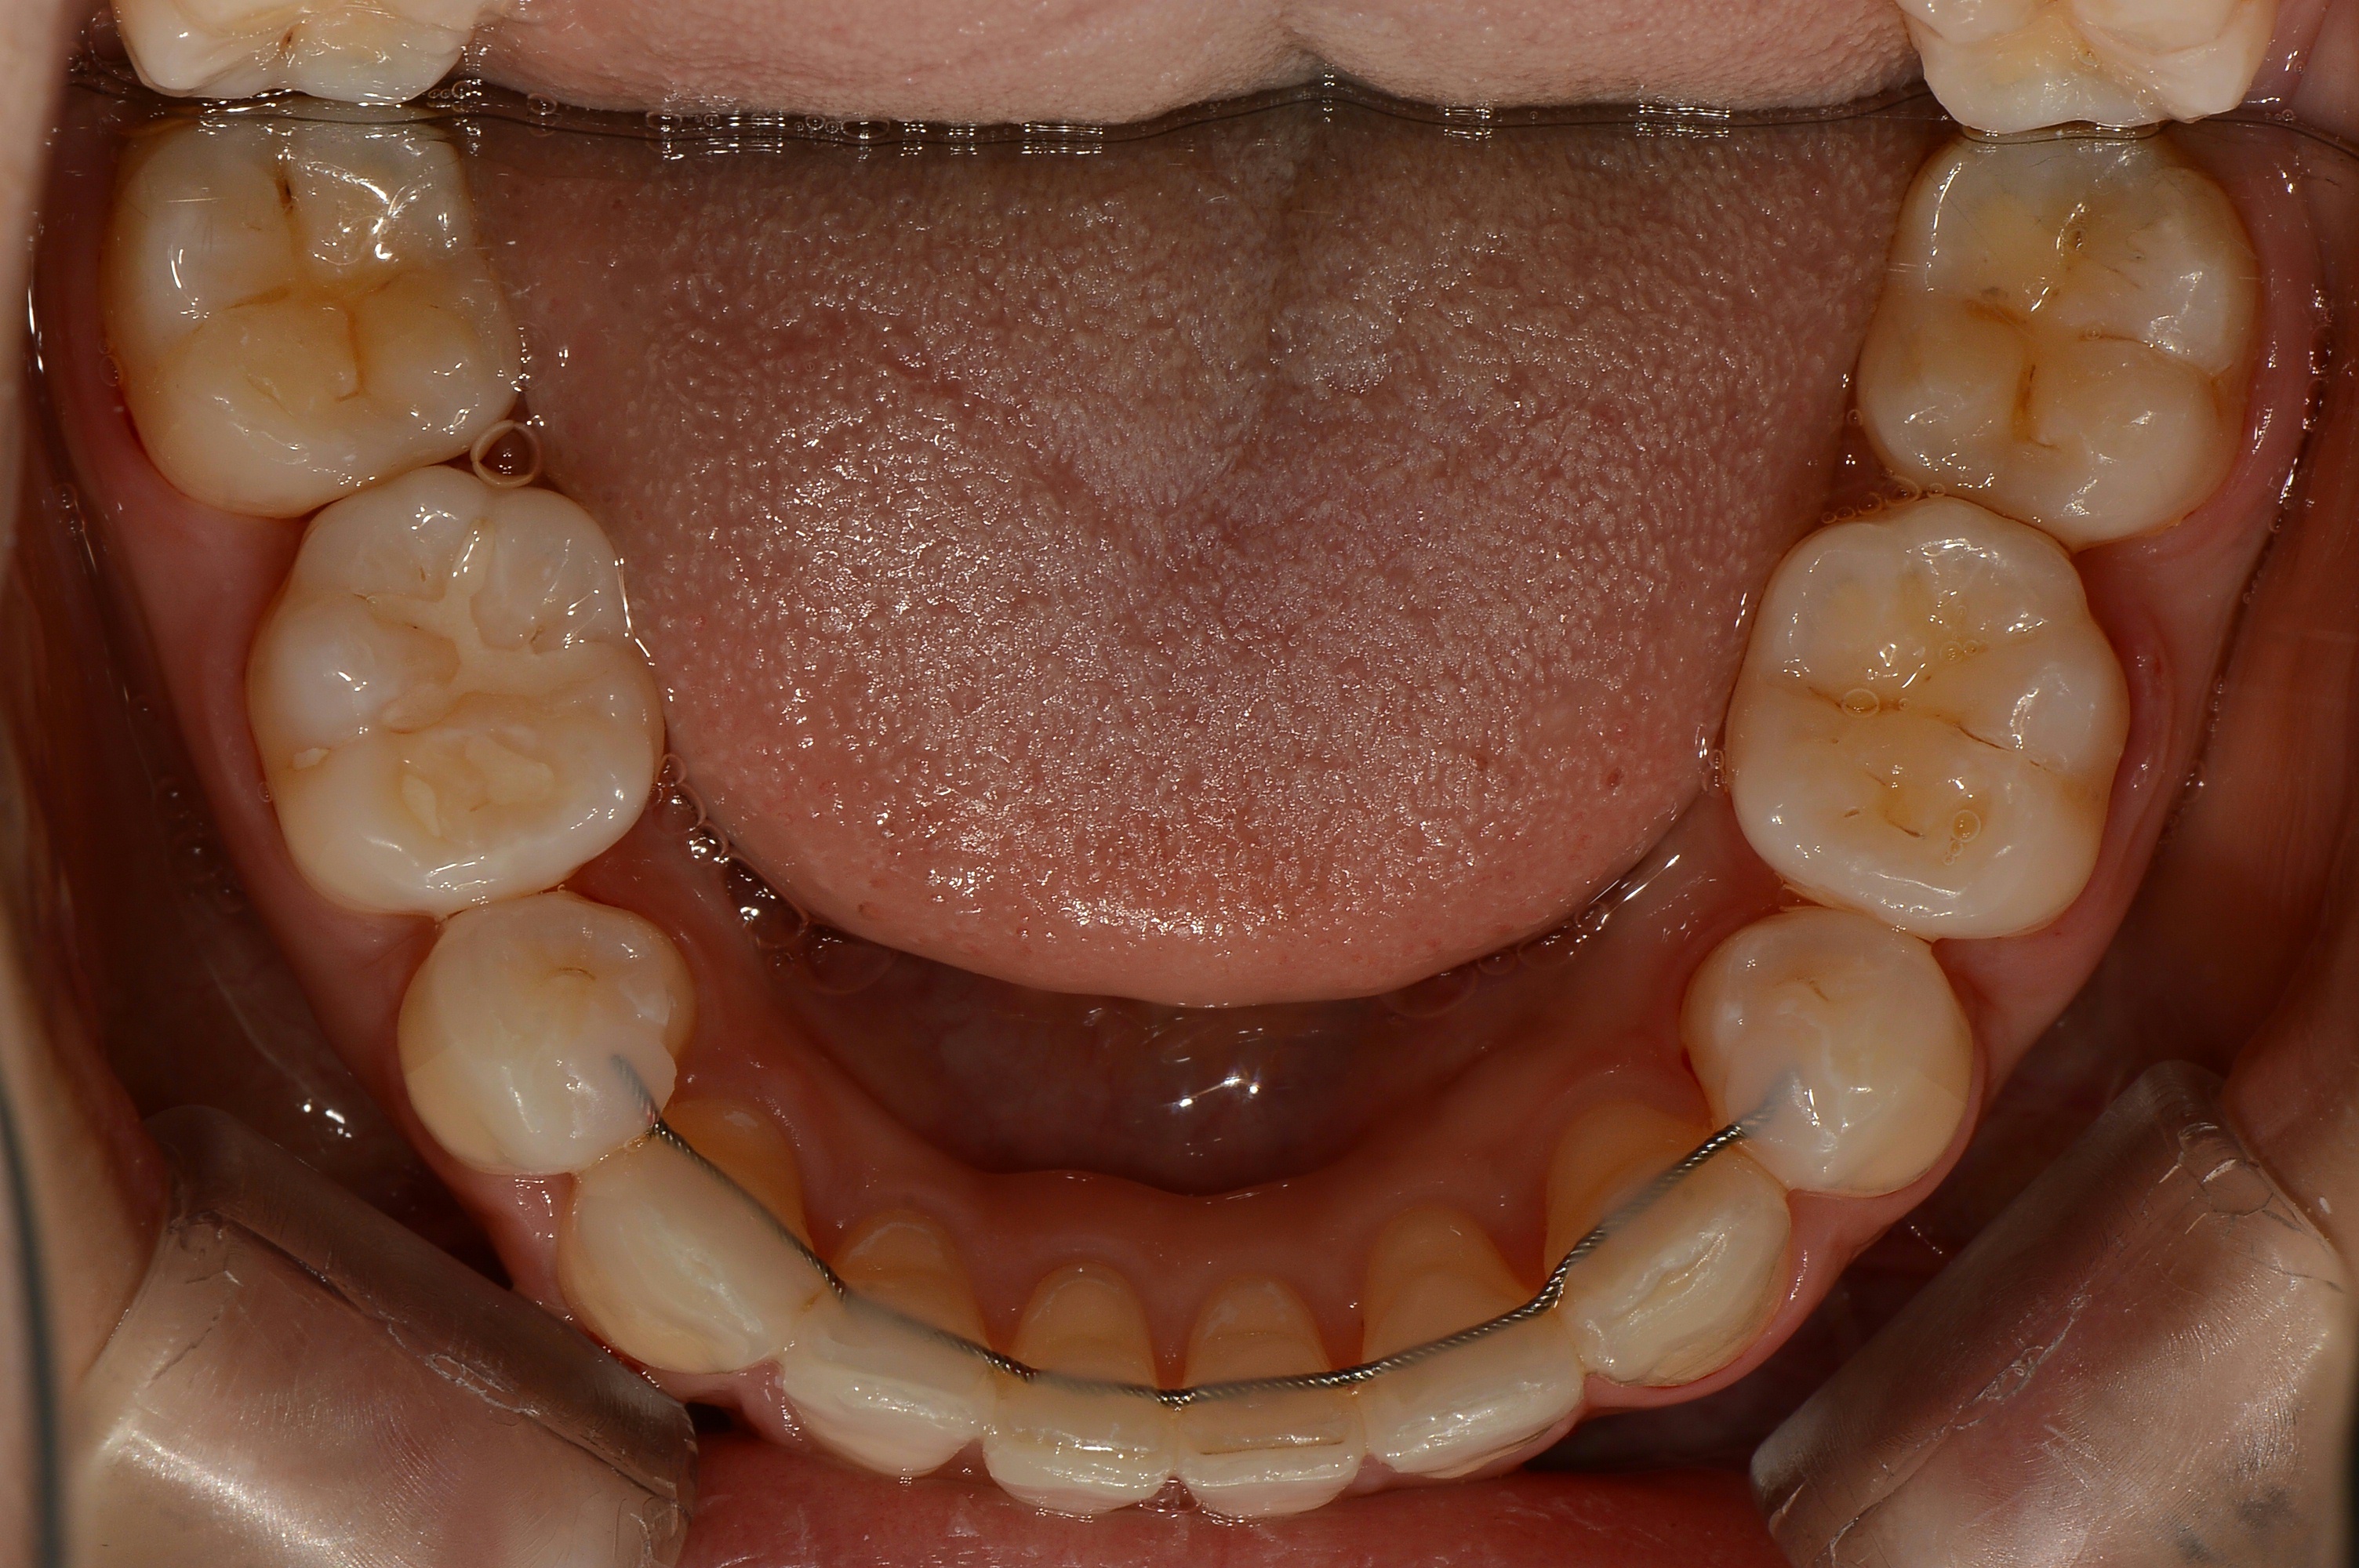

치료 전 사진입니다.